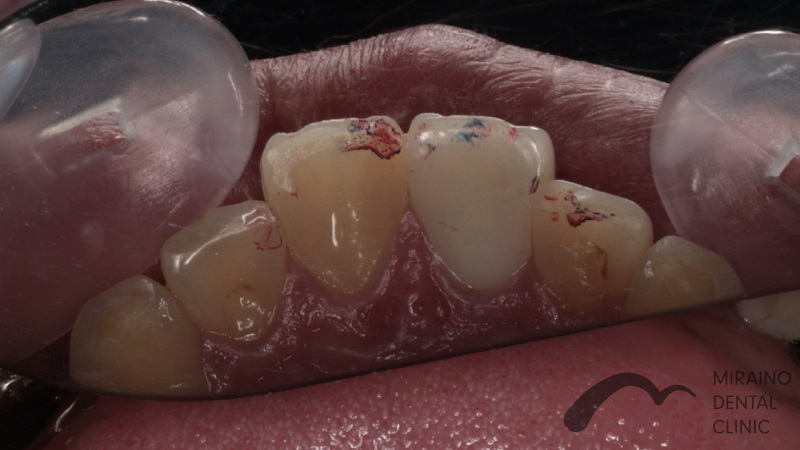

歯の破折予防:MTMの症例

| 施術名 | 歯の破折予防:MTM |

| 施術の概要 | 前歯の差し歯の色が気になるということで来院されました。 噛んだ時に下の前歯が隠れており、治療した歯をより劣化させやすい噛み合わせ[過蓋伵合]の方でした。 歯を失う原因のうち、ムシ歯・歯周病以外に歯への負担荷重お伝えしましたが、 根本的な噛み合わせの治療は希望されなかったため、 次回再発した際は抜歯となる可能性が高いため、なるべく再発しにくい歯科治療を希望され、 MTMを行ったのちメタルフリークラウンでの歯冠修復行いました。 |

クリックして詳細を表示

| 施術の内容 | ムシ歯や歯が折れておりで感染除去後に健康な歯が歯茎の下まで達する場合は、 通常、抜歯もしくは2年以内の抜歯前提の延命治療になってしまいます。 両サイドの歯に表装置をつけ骨からひっぱり出すことで、 歯根破折・歯冠脱離による抜歯の可能性を回避します。 部分矯正MTM(Minor Tooth Movement)の略で、 このような場合エクストルージョン(伾出)と言います。 |

| 1歯あたりの治療費 | 1歯につき50,000円 |

| 考えられるリスク、副作用[歯科治療] | 治療後、痛みや違和感、出血、腫れ、麻痺などが出る事があります。 |

| 考えられるリスク、副作用[全てにおいて] | 必ずしもご希望通りにならない事があります |

| 考えられるリスク、副作用[麻酔] | 麻酔を行う場合、腫れやむくみを生じる事があります。 |

| 考えられるリスク、副作用[噛み合わせ] | また、歯並びが変わる事により違和感を生じる事があります。 |

| 考えられるリスク、副作用[被せ・仮歯] | 仮歯の期間中は仮歯の部分で噛むと破損する場合があります。 |

| 考えられるリスク、副作用[根の治療] | 治療に際して、根の治療が必要になる場合があります。 |